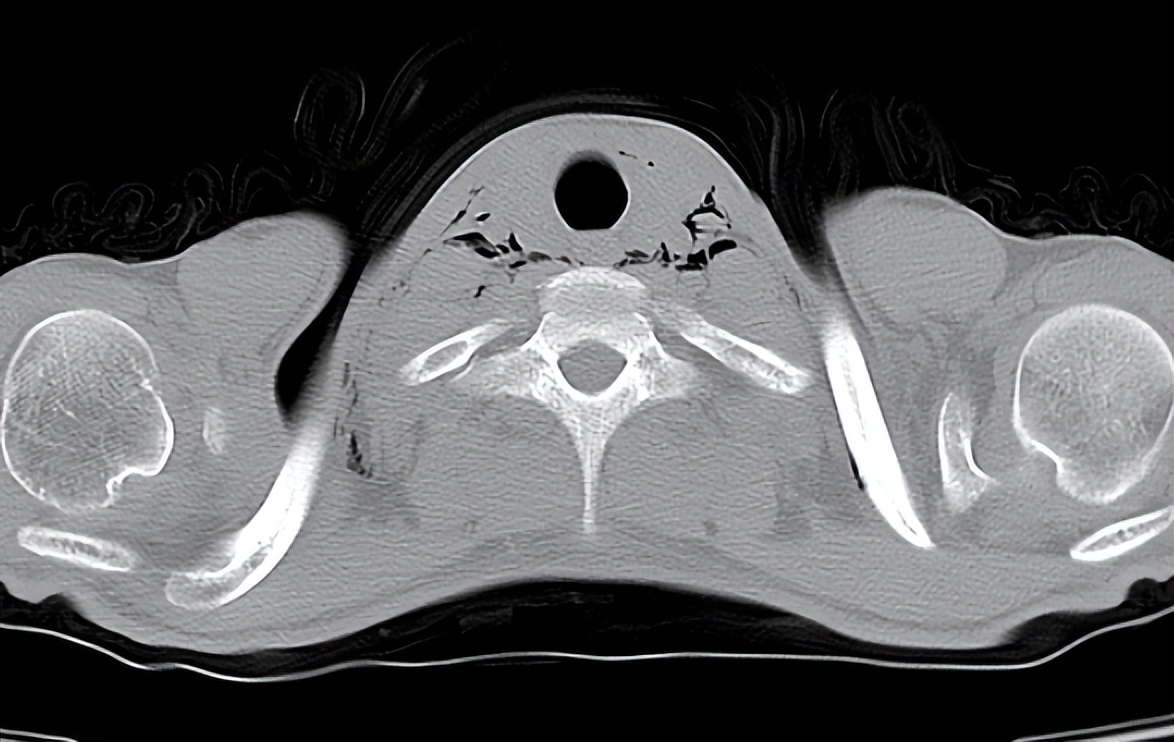

这是一位

纵隔气肿患者的检查报告

经胸部CT可见横断位螺旋扫描层厚5mm,层距5mm。胸廓对称,气管居中,肺支气管血管束规整,未见异常组织密度影及占位性病变。气管、支气管通畅,未见狭窄或阻塞征,肺门影不大。纵隔内及颈根部见散在游离气体密度影。双侧胸膜无增厚,用真实有效的报告确诊了纵隔气肿。